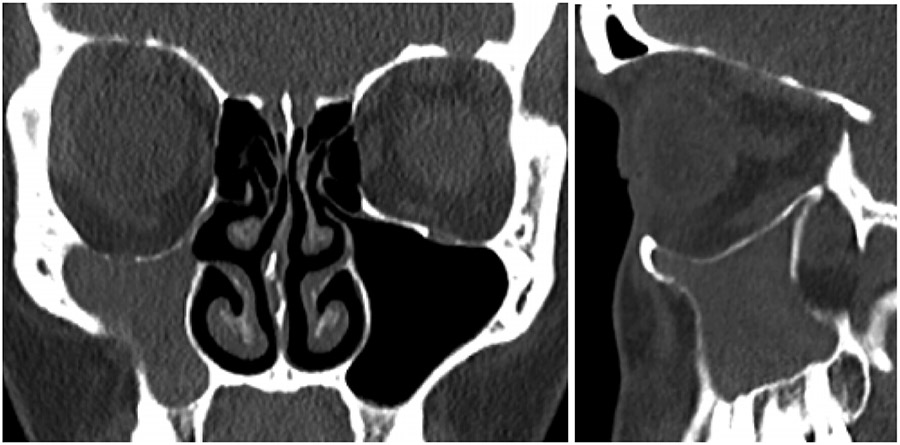

Because of a superior performance over standard implants, patient-specific implants, developed by computer assisted design and computer assisted manufacturing (CAD/CAM) systems, for craniomaxillofacial reconstruction have grown in popularity in the last decade. Customized implants allow a more precise adaptation to the region of implantation, ideal shape and symmetry, with reduced surgical times, and better cosmetic outcomes.

The patient underwent a Caldwell-Luc approach and concurrent orbital floor reconstruction. A one-stage approach was chosen for a faster recovery and single surgery. Correction of enophthalmos and dystopia was performed using a patient-specific CAD/CAM implant (Fig. 3) assisted by intraoperative navigation and CT scan (Fig 4.). The 0.3mm orbital floor titanium plate was placed through a transconjunctival approach (Fig. 5). The patient was found to be complaint free and full recovered at 6th-month follow-up (Fig 1.).